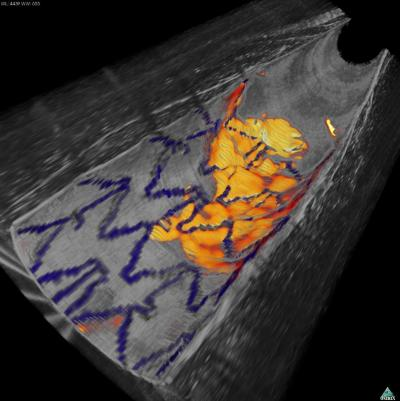

| Combined optical frequency-domain imaging and near-infrared fluorescence image of the inner surface of a rabbit artery shows an implanted arterial stent (blue) and fibrin deposits (red-yellow). By revealing both structural and molecular detail, OFDI-NIRF may improve diagnosis of coronary artery disease and help evaluate stent healing. (Image courtesy of Massachusetts General Hospital) |

Researchers at Massachusetts General Hospital (MGH; Boston, MA) have developed an intra-arterial catheter that mixes optical frequency-domain imaging (OFDI) and near-infrared fluorescence (NIRF) imaging to obtain simultaneous structural and molecular images of internal arterial surfaces.

The team first confirmed that the system could provide detailed structural images of a stent implanted in a cadaveric human coronary artery and could accurately identify the presence of fibrin on the stent. In a series of experiments in living rabbits, the OFDI-NIRF system was able to detect fibrin on implanted stentsâincluding areas where it was not detected by OFDI aloneâand to identify the presence of both atherosclerotic plaques and enzymatic activity associated with inflammation and plaque rupture. The enzyme signal detected by NIRF was not uniform throughout the imaged plaques, indicating biological differences that could be relevant to prognosis and treatment planning.